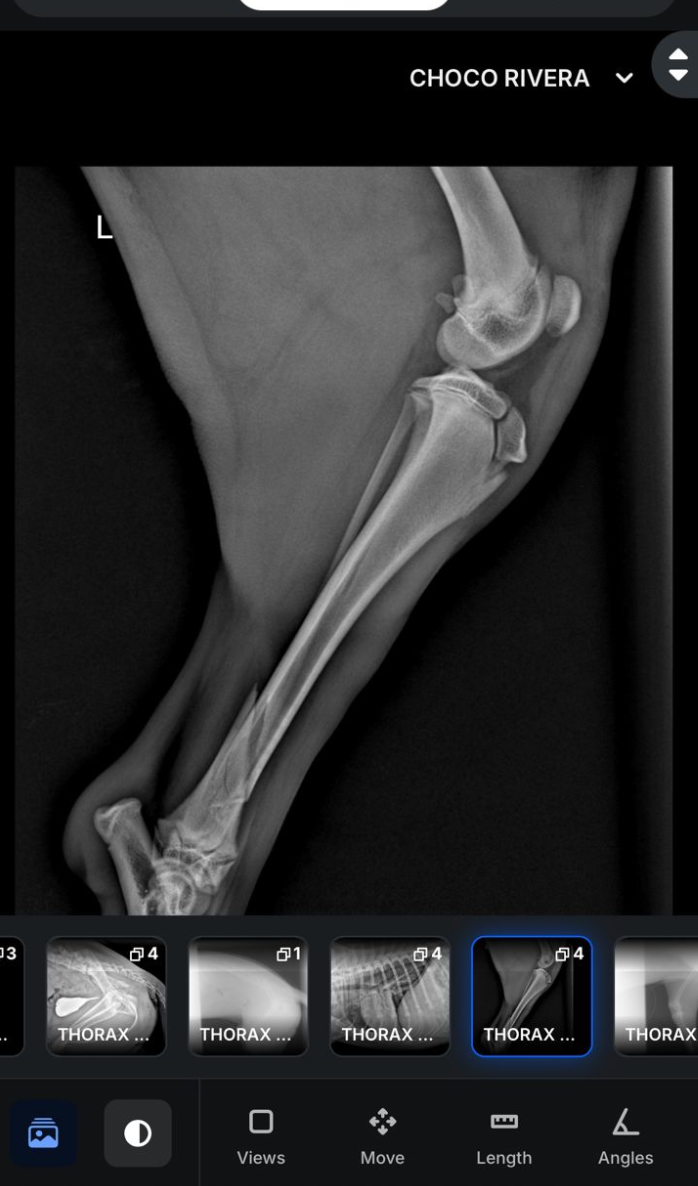

Choco suffered multiple fractures to his leg and hips and required immediate veterinary care. To ensure he received treatment without delay, I covered the upfront emergency costs.

Choco sufrió múltiples fracturas en la pierna y en la cadera, por lo que necesitó atención veterinaria inmediata. Para que pudiera recibir el tratamiento necesario sin ningún retraso, yo cubrí los gastos médicos de emergencia de forma inmediata.